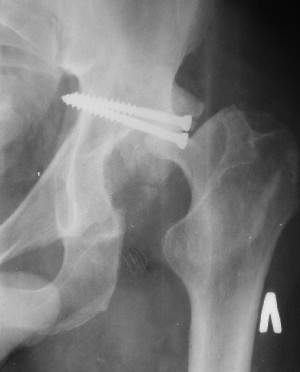

Послеоперационный снимок прямой 5/05/03

Больной 18 мая 2003 года в автоаварии получил перелом левой вертлужной впадины, вывих бедра. Госпитализирован в один из стационаров области.Вывих вправлен. В последствии бедро вывихивалось еще дважды. На консультацию был представлен снимок от 19.05.03г., больной переведен к нам 3.06.03г. Снимок при поступлении - перелом впадины, задне-верхний вывих бедра. 05.06.2003 г. выполнено открытое вправление вывиха левого бедра и остеосинтез стенки вертлужной впадины двумя винтами. Послеоперационный период без осложнений. Объем движений в левом тазобедренном суставе восстановился полностью. Выписан на амбулаторное лечение в удовлетворительном состоянии с рекомендациями 3 месяца ходить на костылях без нагрузки на оперированную конечность. На контрольных рентгенограммах левого тазобедренного сустава 13.10.2003 г. - признаки консолидации перелома; плотность, форма головки и состояние суставных поверхностей удовлетворительные. Разрешена дозированная осевая нагрузка, на конечность с использованием дополнительной опоры. 19.12.2003 г. больной обратился с жалобами на боли в левом тазобедренном суставе. На рентгенограммах левого тазобедренного сустава 19.12.2003 г., 20.02.04г. - асептичекий некроз головки бедра. 5.04.04г. - эндопротез. Сейчас ходит без трости, не хромает. Особенность эндопротезирования - при удалении винтов прослежена линия перелома заднего края впадины и предложено установить чашку несколько меньшего диаметра, чтобы она была покрыта несломанной частью.